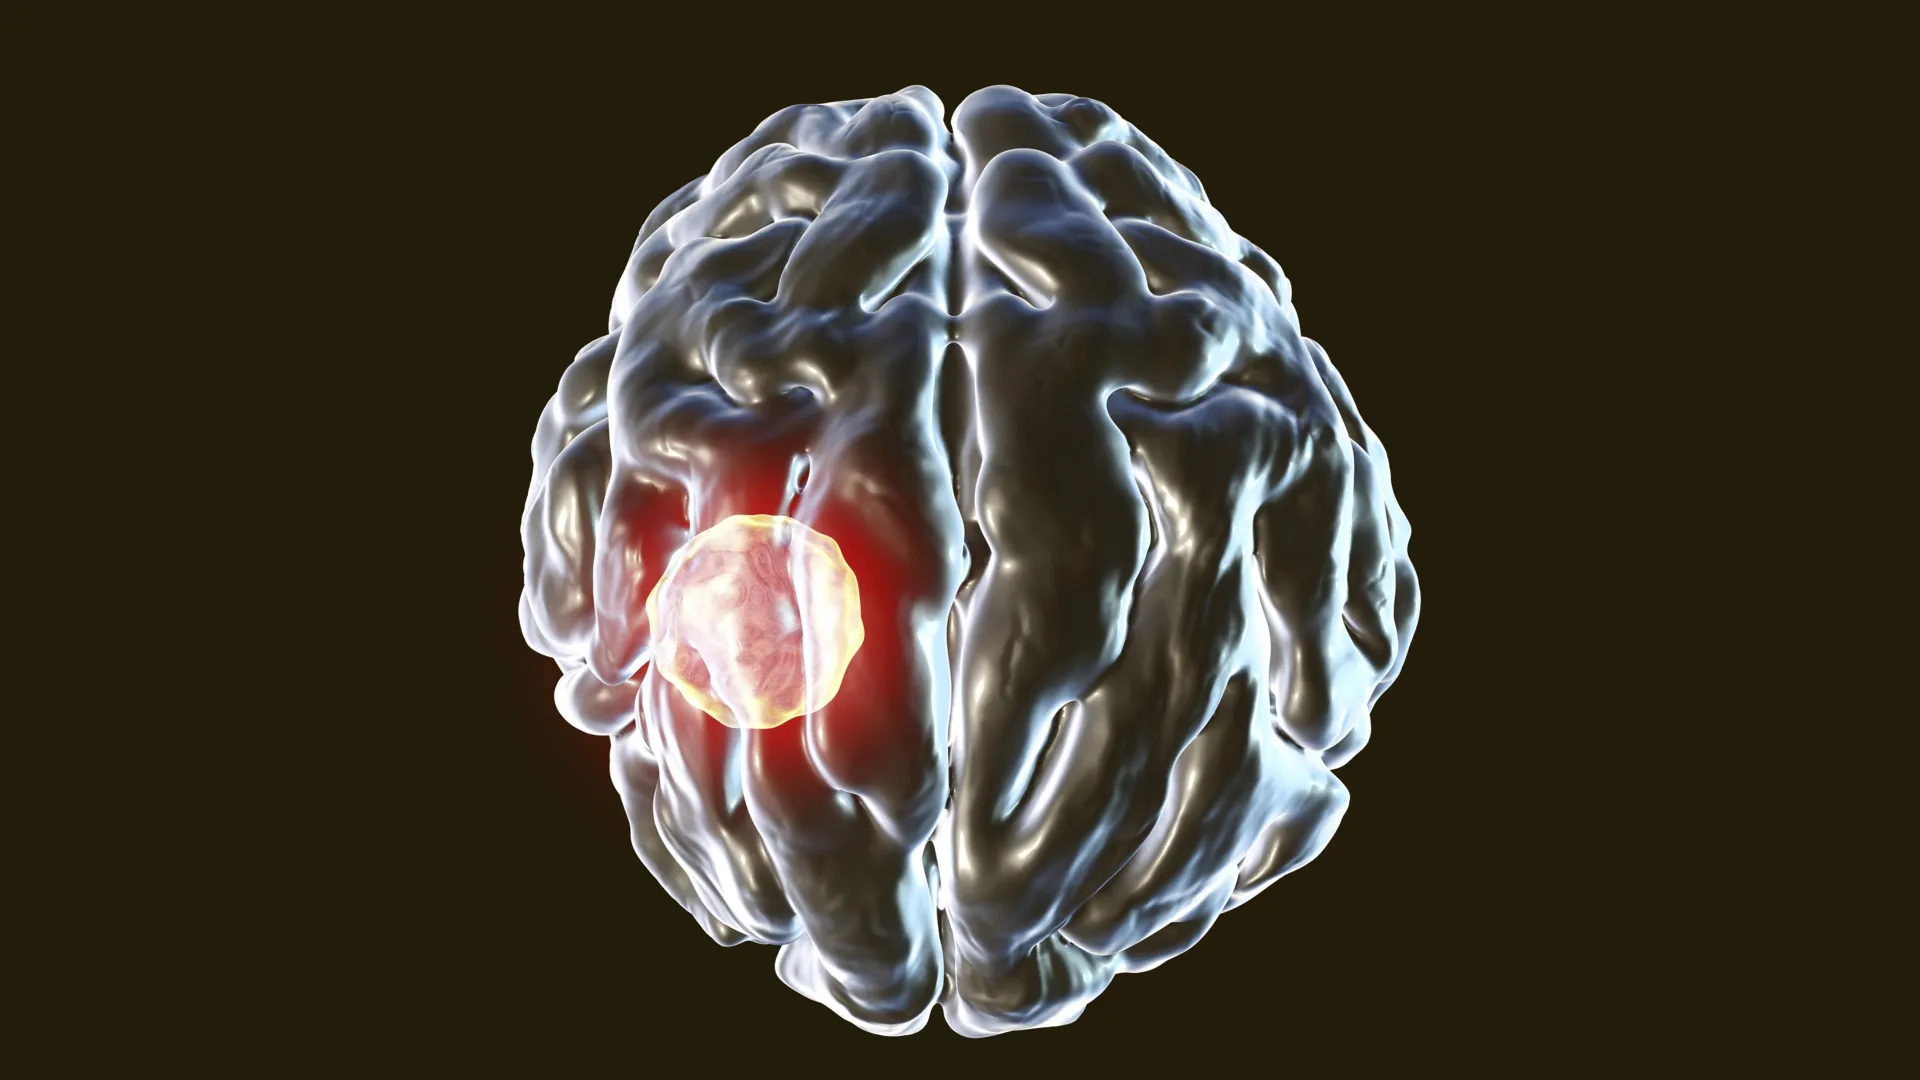

تعتبر العدوى بالطفيلي الدماغي التوكسوبلازما جوندي من المواضيع المهمة في مجال الصحة، حيث يصيب حوالي ثلث سكان العالم. في هذا المقال، نستعرض كيف يحارب الجسم هذه العدوى.

الطفيلي الذي ربما يعيش بالفعل في دماغك لديه القدرة على إصابة الخلايا المناعية ذاتها المصممة للقضاء عليه. يشرح بحث جديد أجرته UVA Health كيف يتمكن الجسم من إبقاء هذه العدوى تحت السيطرة.

التوكسوبلازما جوندي هو طفيل خطير يصيب الحيوانات ذوات الدم الحار. غالبًا ما يتعرض الأشخاص للعدوى من خلال الاتصال بالقطط أو الفواكه أو الخضروات الملوثة أو اللحوم غير المطبوخة جيدًا. بعد دخول الجسم، يمكن للطفيلي أن ينتشر إلى أعضاء متعددة ويستقر في النهاية في الدماغ، حيث يمكن أن يبقى مدى الحياة. ويعتقد أن ما يقرب من ثلث سكان العالم يحملون داء التوكسوبلازما، ولكن معظم الناس لا تظهر عليهم الأعراض أبدًا. عندما يحدث المرض، المعروف باسم داء المقوسات، فإنه يكون أكثر خطورة لدى الأفراد الذين يعانون من ضعف في جهاز المناعة.